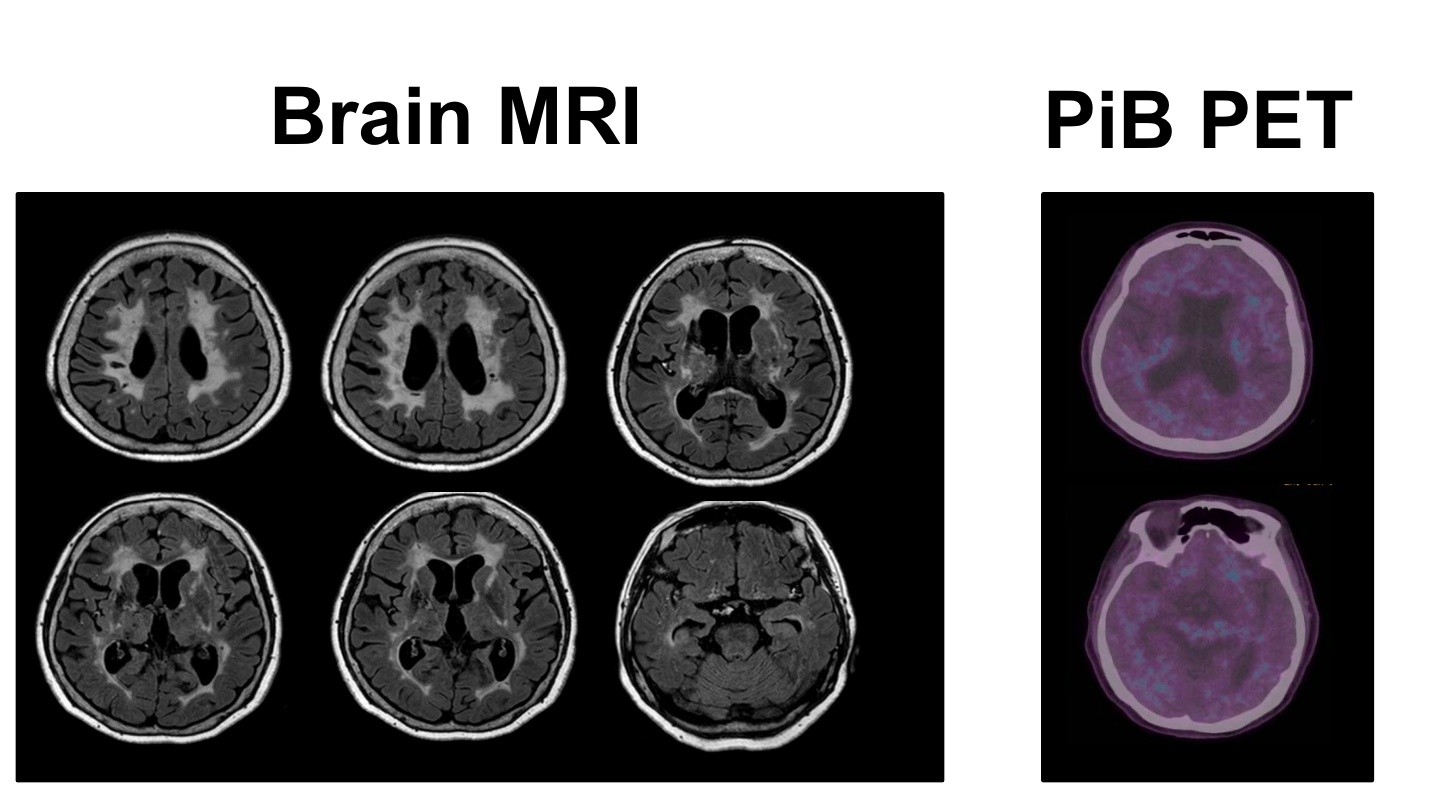

현재 삼성서울병원 신경과 교수로 재직 중이신 김준표 교수님은 신경과 레지던트, 전임의, 임상조교수로 활동하시며 대한치매학회 위원으로서 치매와 신경과학 분야에서 깊은 전문성과 풍부한 경력을 쌓아오셨습니다. 특히, SCI급 논문 55편을 게재하며 학문적 연구에도 크게 기여하셨습니다. 이번 강연에서는 치매의 진단, 치료, 예방에 대한 귀중한 통찰을 나눠주실 예정입니다.

현대사회에서 치매는 우리 주변에서 점점 더 빈번하게 접할 수 있는 중요한 건강 문제로 떠오르고 있습니다. 이번 강의를 통해 치매를 진단하고, 효과적으로 치료하며, 예방할 수 있는 실질적인 방안에 대해 알아볼 수 있는 소중한 시간을 가질 수 있을 것 같습니다. 치매 분야에서 오랜 경험을 지닌 교수님의 강의를 통해 치매에 대한 더 깊은 이해와 대비책을 마련할 기회를 함께 가져보시길 바랍니다.